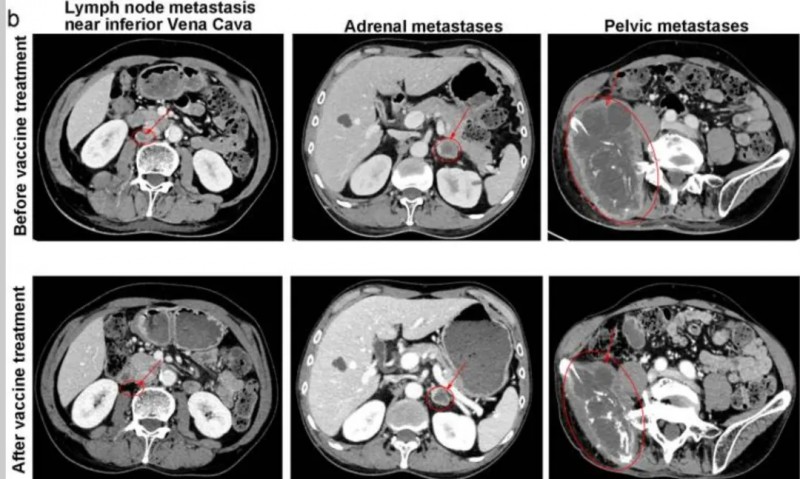

肺腺癌:肿瘤缩小29%

这位患者同样也经历三线化疗、放疗和PD-1抑制剂治疗失败,在Neo-DCVac治疗后,肿瘤靶病灶缩小了29%。